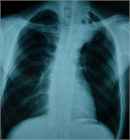

1. 嗄声を来した患者では、喉頭ファイバーにて声帯の麻痺の有無を調べることが推奨される(推奨度1)

1. 反回神経麻痺を来した患者では、頭頸部~胸部部位の診察とCT検査などの画像検査を行うことが推奨される(推奨度1)